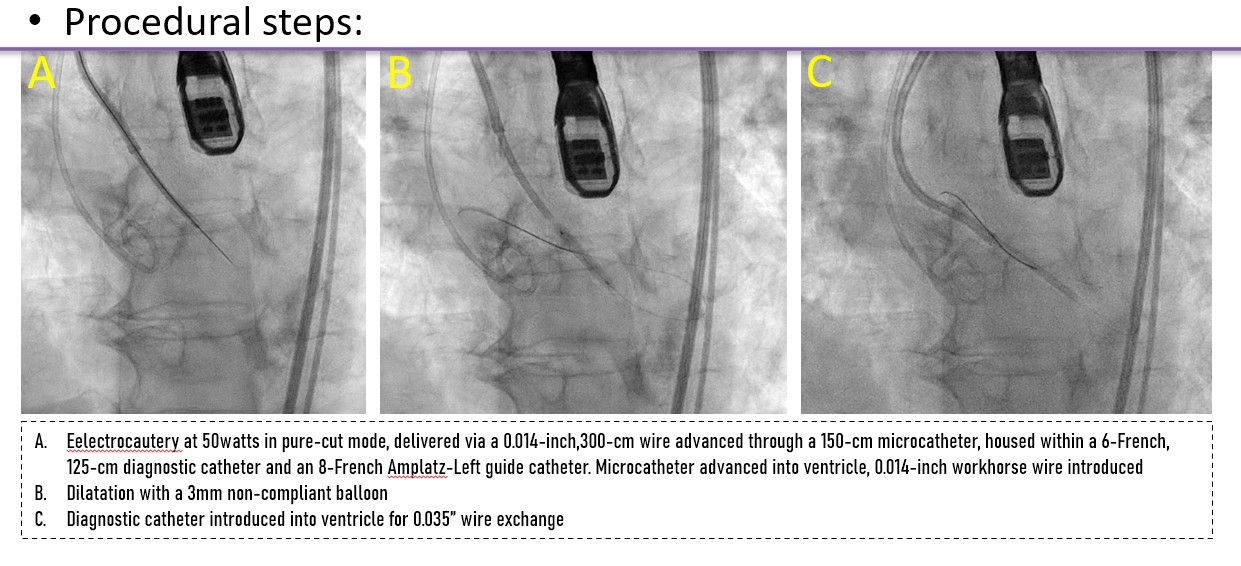

A controlled laceration of the native left coronary cusp was planned under general anaesthesia. A puncture point 2 mm above the cusp base, aligned with the coronary ostium, was selected to ensure optimal leaflet splay and minimise recoil risk following laceration. Leaflet traversal was performed using electrocautery at 50 W in pure-cut mode, delivered through a 0.014-inch, 300-cm Astato wire (ASAHI) advanced via a 150-cm Finecross microcatheter (Terumo), housed within a 6-French, 125-cm multipurpose diagnostic catheter and an 8-French Amplatz Left guide catheter. After advancing the microcatheter into the left ventricle, the Astato wire was exchanged for a 0.014-inch Fielder wire. Initial dilatation was performed using a 3 mm non-compliant Apollo balloon (BrosMed Medical). The Fielder wire was then exchanged for a 0.035-inch, 260-cm J-tip wire, and subsequently for a pre-shaped Safari wire (Boston Scientific). Based on procedural planning, a balloon size equal to or up to 2 mm shorter than the leaflet length was deemed adequate to achieve effective laceration while avoiding sinus or annular injury. Controlled leaflet laceration was performed using sequential balloon dilatations with an 8-mm Armada balloon (Abbott Cardiovascular) followed by a 12-mm Mustang balloon (Boston Scientific). Successful laceration was indicated by a sudden give-way of the balloon waist, inward balloon shift toward the lumen, and a drop in diastolic pressure. A balloon-expandable valve was implanted.